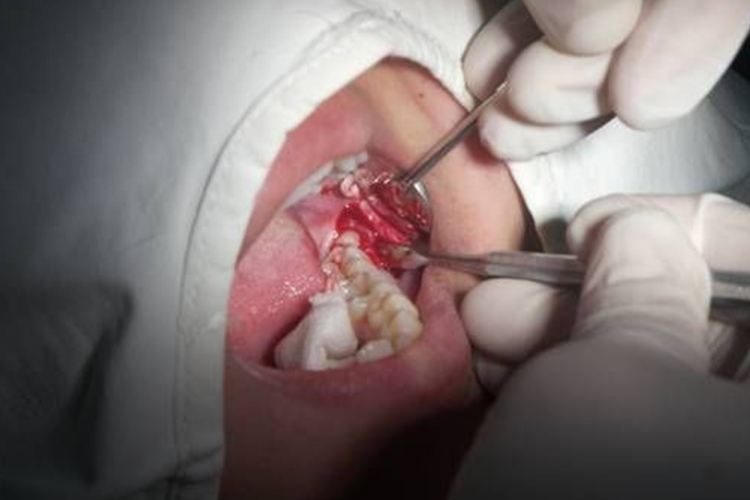

分离牙龈:切开并掀起软组织瓣显露手术野,将牙龈分离器插入龈沟内,紧贴牙面伸入到沟底,沿牙颈部推动,分离牙龈。此步骤可避免安放牙钳或拔牙时出现牙龈撕裂。

挺松患牙:对于阻生牙、坚固不易拔除的智齿,因不能用牙钳夹住,需应先用牙挺将牙挺松或用涡轮钻去骨、离断阻生齿后再拔除。

安放牙钳:将钳喙分别安放于患牙的唇颊、舌腭,钳喙的纵轴与牙长轴平行。到龈下部位,达牙根部的牙骨质面与牙槽嵴之间。手握钳柄近末端处将患牙夹牢。